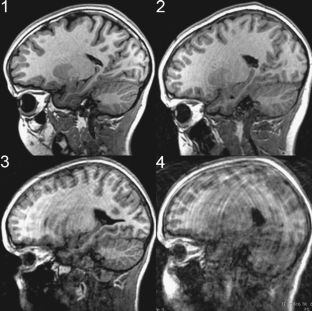

A new technique for prospectively correcting head motion (called PROMO) during acquisition of high-resolution MRI scans has been developed to reduce motion artifacts. To evaluate the efficacy of PROMO, four T1-weighted image volumes (two with PROMO enabled, two uncorrected) were acquired for each of nine children. A radiologist, blind to whether PROMO was used, rated image quality and artifacts on all sagittal slices of every volume. These ratings were significantly better in scans collected with PROMO relative to those collected without PROMO (Mann-Whitney U test, P < 0.0001). The use of PROMO, especially in motion-prone patients, should improve the accuracy of measurements made for clinical care and research, and potentially reduce the need for sedation in children.